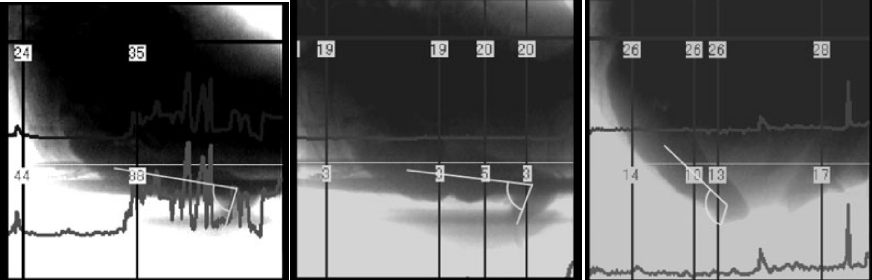

从左到右依次为坐姿、坐姿踩小板凳、蹲姿的直肠-肛门角,图片来源:参考文献2

2010 年发表在《下尿路症状》(lower urinary tract symptoms)上的一项研究,就找来了 6 名志愿者,研究了他们在 3 种拉便便姿态下的直肠-肛门角,这三种姿态分别是坐姿、坐姿外加脚踩小板凳、蹲姿。

结果发现,不同姿态下直肠-肛门角度之间确实存在差异。

坐在马桶上,直肠-肛门角的平均度数为 100°,坐在马桶上踩着小板凳,平均度数为 99°,而在蹲姿状态下,这一度数平均值是 120°。所以,在这三种拉便便姿态下,蹲坑的姿态确实能够让“便便的通道”更顺畅。

为了更进一步研究三种姿态对拉便便的影响,研究者往实验者的直肠里注入了造影剂,让他们以三种不同的姿态进行模拟排便,并且记录这些姿态下腹部的压力。

结果发现,在三种姿态下,坐姿状态下实验者需要额外施加的腹部压力最大,其次为坐姿踩着小板凳,在蹲姿状态下实验者需要额外施加的力最小。

不踩小板凳与踩小板凳,直肠-肛门角变化,图片来源:参考文献2